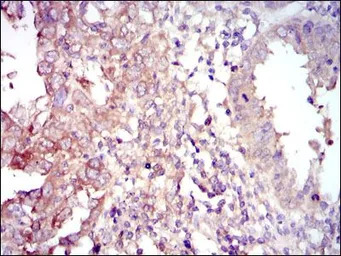

IHC-P analysis of intima cancer tissue using GTX60558 FOXO1 antibody [3B6].